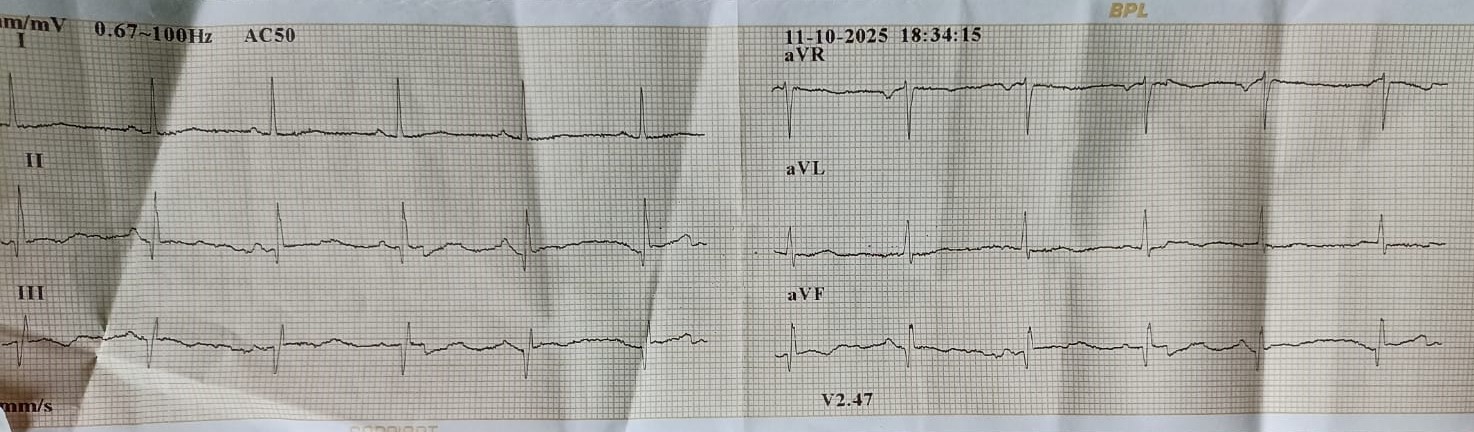

Hemoglobin: 14.6 gm/dLFasting Blood Glucose: 98 mg/dLS. Creatinine: 1.2 mg/dLLDL-C: 121 mg/dLECG: sinus rhythm, Q in lead III, aVF, LVH2D Echo: Inferobasal wall hypokinesia, LVEF 48%

Coronary Angiogram done elsewhere via right femoral artery with JR and AL 1.0LMCA NormalLAD Type III Vessel. Normal. LCx: Non dominant, NormalRCA: Chronic Total Occlusion from midpart. Distal filling by retrograde from Left system.J-CTO score 3